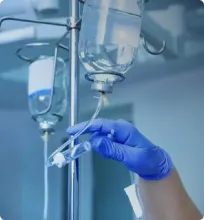

Лечение анорексии требует комплексного подхода, так как болезнь затрагивает не только физическое состояние, но и психику. Расстройство пищевого поведения часто начинается незаметно, но приводит к тяжёлым последствиям: снижению веса, разрушению здоровья, социальным проблемам. Эффективное лечение включает медицинскую помощь, психотерапию, поддержку семьи.